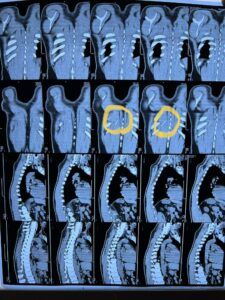

تمكن فريق جراحي بمستشفى بنها الجامعي بمحافظة القليوبية، في استخراج إبرة تنجيد دخلت عن طريق الخطأ في ظهر مريض خلف القفص الصدري مباشرة، والتي ظلت بمكانها مدة عامين.

وأوضحت المستشفى، في بيان لها اليوم، أنه جرى إجراء جراحة بفتح جراحي صغير 3 سم، استخراج “إبرة تنجيد”، دخلت بطريق الخطأ في ظهر مريض خلف القفص الصدري مباشرة، حيث تركها المريض لمدة سنتين خوفا من إجراء العملية.

وتابعت، أنه تم حجز المريض بالقسم وتجهيزه لعملية سريعة، جرى فيها الاستعانة بجهاز الأشعة الملحق بغرف العمليات (C-arm)، حيث تم تحديد مكان الإبرة والفتح الجراحي عليها مباشرة، واستخراجها بنجاح ،ولكن على هيئة قطع منكسرة بسبب الصدأ، نظرا لبقائها طوال هذه المدة.